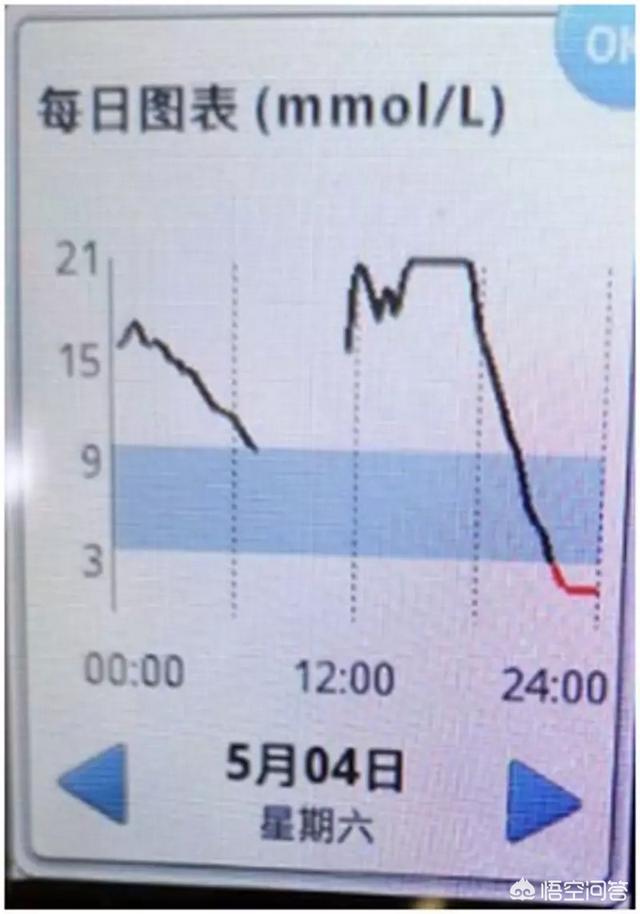

以下は、血糖値の低下が速すぎる、ダイナミック・グルコース・メーターを装着した糖質患者のグルコース・グラフである:

この患者の血糖値は18時過ぎに崖から落ち、21時から24時まで重度の低血糖となった。